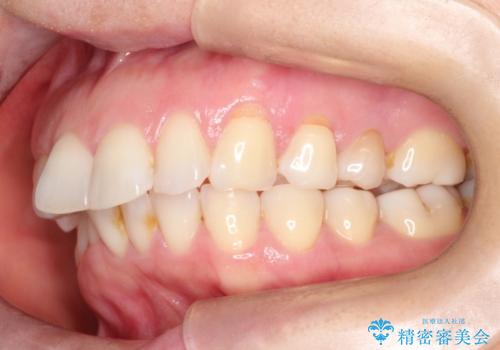

審美装置を用いたワイヤー矯正|非抜歯で歯の凸凹を改善

- 患者様は**歯の凸凹(叢生)**を気にされて来院されました。診査の結果、歯列のスペースが不足しているものの、抜歯をせずに改善できる状態でした。そこで、目立ちにくい審美装置(白いブラケットとホワイトワイヤー)を使用したワイヤー矯正を提案しました。歯列のアーチを広げながら、適宜IPR(歯の幅をわずかに調整する処置)を行い、非抜歯で自然な歯並びへと導く計画を立てました。

治療では、白いブラケットとホワイトワイヤーを使用し、矯正装置が目立ちにくいよう配慮しました。歯列を拡大しながら適切に歯を移動させ、IPRを併用することで、無理なくスペースを確保しました。見た目に配慮しながら、歯の凸凹をスムーズに整え、噛み合わせも改善。患者様からは「装置が思ったより目立たず、歯並びがきれいになって嬉しい」との声をいただきました。